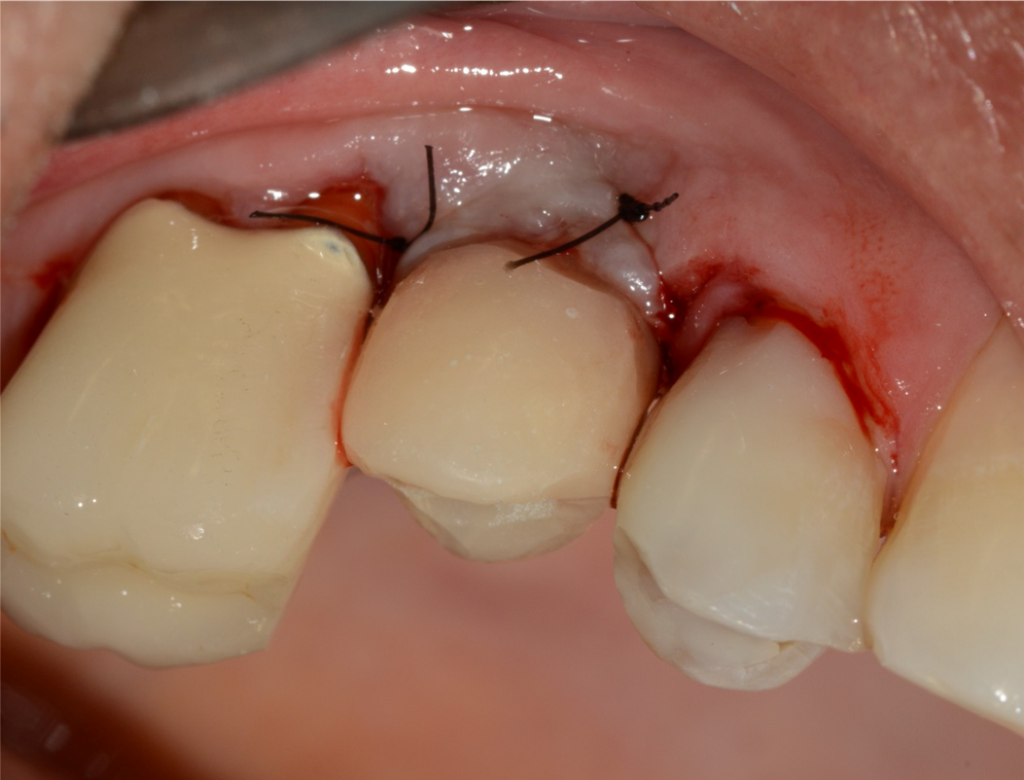

No presente caso, o paciente procurou nossa clínica acreditando que a coroa sobre implante do 15 estava apenas frouxa, e que seria possível resolver apertando o parafuso. Ao exame clínico, apresentava uma coroa cimentada sobre componente UCLA fundida e parafusada diretamente sobre o hexágono do implante (um HE de 3.5 mm de diâmetro e plataforma da mesma medida). Após o corte da coroa para acessar o parafuso, na remoção do conjunto, a plataforma do implante veio anexada à coroa, denotando a fratura do implante, que foi comprovada com radiografia periapical (Figuras 1 e 2). Decidimos por fazer uma prótese adesiva provisória (Figuras 3 e 4) e planejar a remoção do implante com colocação imediata de novo implante, após observado na tomografia cone beam que haveria osso suficiente para isso (Figura 5). O implante foi removido (Figuras 6 e 7) com o uso de broca trefina e fórceps, e um implante Implacil De Bortoli CM Due Cone foi instalado no mesmo momento (Figura 8), com regeneração óssea guiada (ROG) na parede vestibular (Figura 9), que havia ficado muito fina (enxerto ósseo particulado + membrana de colágeno). Apesar de termos obtido bom travamento do implante (45 Ncm), optamos por deixá-lo sem carga pelo período de cinco meses, para respeitar o tempo da ROG (Figuras 10 e 11).

Aguardado o tempo, foi realizada a reabertura do implante com incisão deslocada para a palatal, deixando mais mucosa ceratinizada por vestibular (Figura 12). Foi instalado um Pilar Ideale (Figura 13) e confeccionado um provisório parafusado sobre ele. As suturas acomodaram a mucosa sobre o provisório, conformando-a ao perfil de emergência desejado (Figura 14).